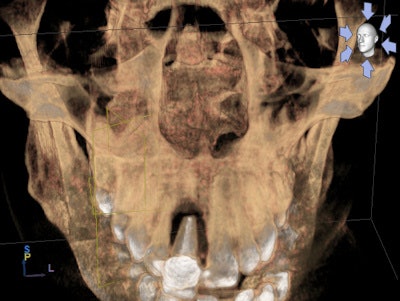

The CBCT images were impressive and became the foundation for my complete dental examination. Incidentalomas were numerous: multiple periapical pathologies and moderate to severe periodontal disease. Although he presented for his maxillary incisor, I was able to capture his attention and devise a pragmatic plan to improve the overall prognosis for his entire dentition.

A challenging road lay ahead as multiple disciplines of dentistry would be necessary to return a poorly maintained dentition to a healthy fully functioning one. Note that multiple asymptomatic periapical lesions existed with #3, #12, #13; multiple teeth were missing; and there was generalized severe periodontal breakdown.